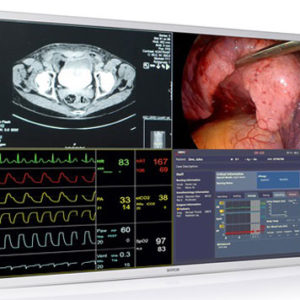

Monitor Medico – LMD-2435MD

El LMD-2435MD muestra imágenes y vídeos en 2D procedentes de cámaras endoscópicas, laparoscópicas y otros sistemas de escáner médicos compatibles. Se ha mejorado su funcionamiento flexible con una selección de modos de imagen, mientras que una interfaz de usuario intuitiva asiste al usuario con tan solo pulsar unas teclas. Diseñado para su integración en los entornos quirúrgicos actuales, el monitor se puede instalar cómodamente en el techo o integrarse en un carrito médico moderno. Las interfaces analógicas y digitales simplifican la conexión con una amplia gama de fuentes de imagen de HD y Definición Estándar.

SKU: n/a - Monitores Médicos, Monitores Sony

Monitor Medico – LMD-2735MD

El LMD-2735MD muestra imágenes y vídeos en 2D procedentes de cámaras endoscópicas, laparoscópicas y otros sistemas de escáner médicos compatibles. Se ha mejorado su funcionamiento flexible con una selección de modos de imagen, mientras que una interfaz de usuario intuitiva asiste al usuario con tan solo pulsar unas teclas. Diseñado para su integración en los entornos quirúrgicos actuales, el monitor se puede instalar cómodamente en el techo o integrarse en un carrito médico moderno. Las interfaces analógicas y digitales simplifican la conexión con una amplia gama de fuentes de imagen de HD y Definición Estándar.